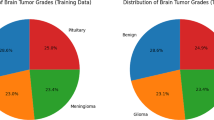

Brain tumors are one of the leading causes of death worldwide. Different types of brain tumors are known, so the choice of treatment depends directly on the type of tumor. The classification of brain tumors is very important as a complex and challenging problem in the field of image processing. Today, deep learning methods are used to classify brain tumors. In addition to being able to detect and automatically classify all types of brain tumors, these methods significantly reduce the diagnosis time and increase accuracy. In this paper, a deep learning-based model is proposed to classify brain tumors into three classes: glioma, meningioma, and pituitary tumor. In the first phase, the pre-trained network ResNet50 is used to extract features from MRI images. In the second phase, by proposing two attention mechanisms (depth-separable convolution-based channel attention mechanism and an innovative multi-head-attention mechanism), the most effective spatial and channel features are extracted and integrated. Finally, the classification phase is performed. Evaluations on the Figshare dataset showed an accuracy of 99.32%, which performs better than existing models. Therefore, the proposed model can accurately classify brain tumors and help neurologists and physicians make accurate diagnostic decisions.